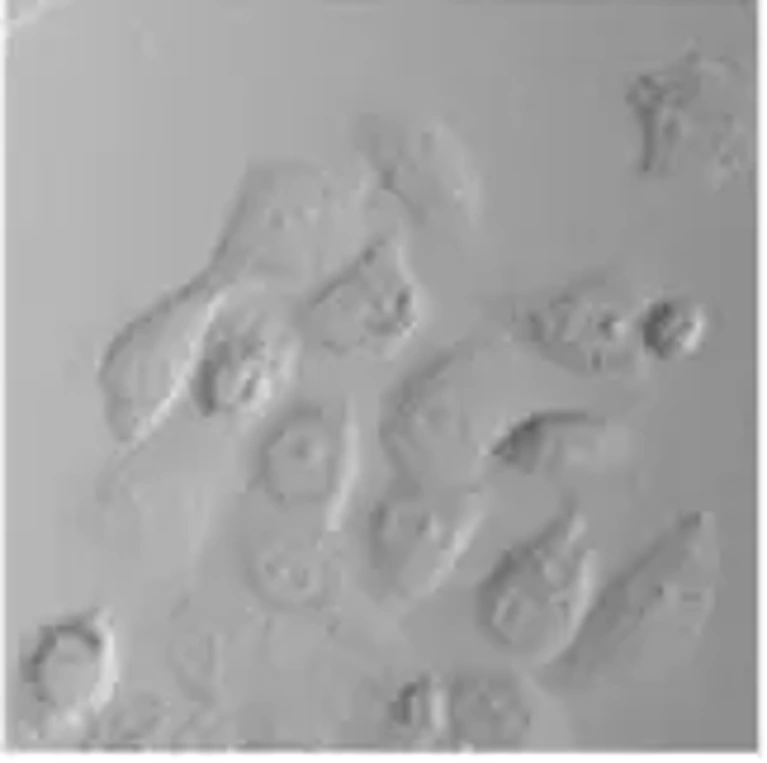

The A-253 human epithelial cell line is a long-established, widely used and characterized cell line originally derived from a salivary gland epidermoid carcinoma of submaxillary gland. The cell line is an established in vitro model for studies of salivary gland tumor biology and squamous cell carcinoma-like epithelial malignancies. A-253 cells exhibit a characteristic epithelial morphology, growing as an adherent monolayer of polygonal cells with distinct cell-cell contact. For these reasons, the A-253 cell line has also been used for studies into epithelial differentiation, adhesion and tumor progression.

After treating A-253 cells with free Ceb, Cu-p-NC, and Ceb-Cu-p-NC, cell viability was assessed using DAPI staining and fluorescence microscopy. Figure 1A shows reduced fluorescence intensity in small hemispherical nuclei following treatment. Optimal doses of these formulations significantly increased apoptosis, with Ceb-Cu-p-NC showing a more pronounced effect than free Ceb. Specifically, 25 µg/mL of Ceb-Cu-p-NC reduced A-253 cell viability, indicating persistent DNA damage. The IC50 values for Ceb in Ceb-Cu-p-NC were 27.55 µg/mL, 41.35 µg/mL, and 51.47 µg/mL after 24, 48, and 72 hours, respectively. Figures 1A and 1B illustrate a time- and dose-dependent anticancer effect against the A-253 cell line. Ceb-Cu-p-NC's controlled release from 24 to 72 hours resulted in higher cytotoxicity than free Ceb, achieving approximately 81.25% reduced cell viability at different concentrations. Therefore, the optimal concentration of Ceb-Cu-p-NC is 25 µg/mL to achieve nearly 80% of reduced cell viability (Fig. 1B). Copper compounds have a potential anticancer effect on their own or in combination with other drugs by altering the DNA regulation processes, cell cycle checkpoints, and apoptotic pathways. It can be concluded that Cu-based polymeric modifications are potent in targeted anticancer drug delivery with different release patterns. Folate-decorated nanostructured lipid carriers for the co-delivery of cisplatin and paclitaxel exhibit excellent anticancer effects in head and neck cancer. The obtained results will make this carrier a potential future work for a dual-drug delivery system.